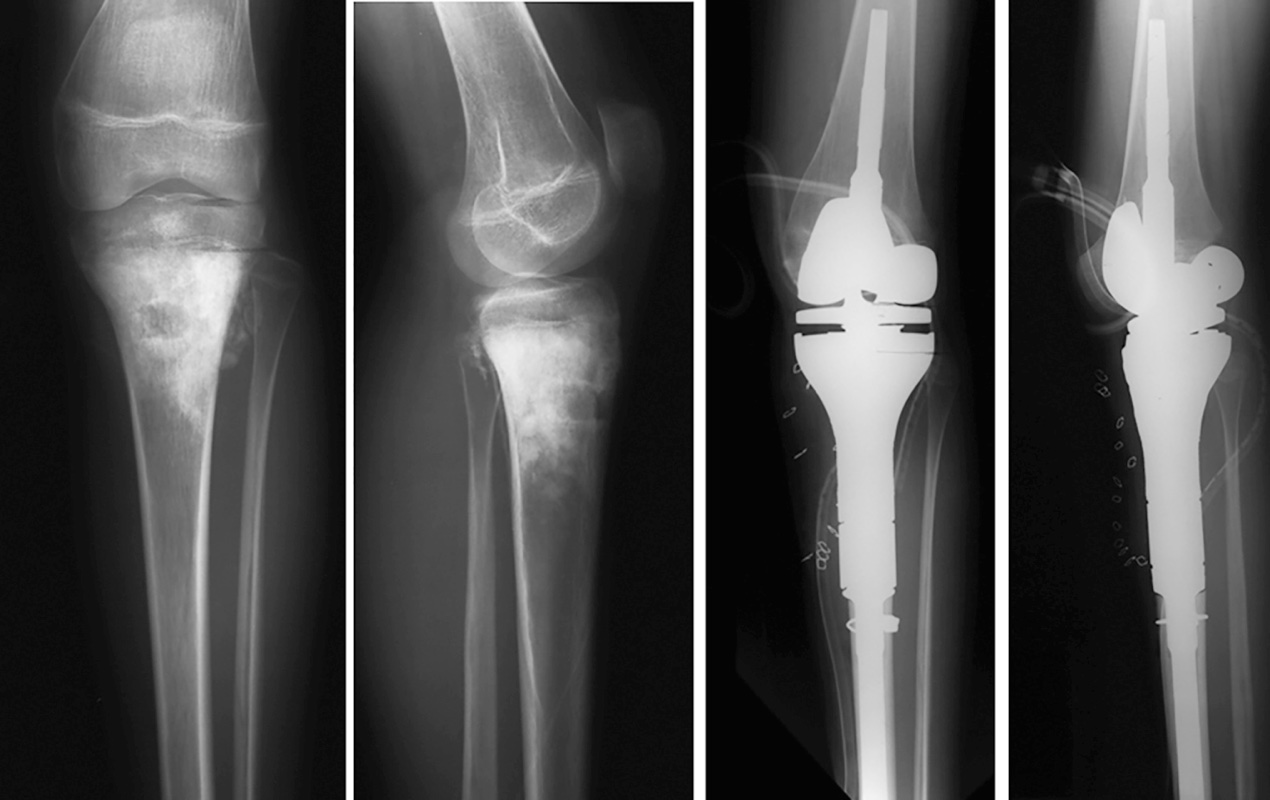

Una volta completata l’asportazione del tumore il pezzo operatorio viene misurato per determinare le dimensioni del difetto che si è creato e per assemblare le componenti di prova che serviranno per fare le prove prima dell’impianto definitivo. Si procede quindi ad alesare il canale diafisario per l’impianto degli steli prescelti e si procede quindi a preparare l’articolazione adiacente per ricevere la protesi. Quindi la protesi di prova viene assemblata e impiantata. Il chirurgo valuta a questo punto, la lunghezza dell’impianto, la stabilita e l’articolarità. Eventuali dismetrie possono essere a questo punto corrette sostituendo le componenti con un segmento più lungo o più corto in base alla necessità. Una volta ottenute le dimensioni reali dell’impianto si procede ad assemblare la protesi definitiva che viene in seguito impiantata cementando o meno gli steli.

La terza fase prevede la copertura della protesi con i tessuti molli per consentire la necessaria stabilita e funzionalità della protesi. Una completa copertura della protesi e essenziale per minimizzare il rischio di deiscenza della ferita chirurgica e di sovra infezione. Per garantire un adeguata funzionalità della protesi i vari gruppi muscolari vano suturati direttamente alla protesi. Nel caso di protesi di femore prossimale è utile il mantenimento se possibile della capsula articolare. Se questo non è possibile, allora risulta fondamentale la reinserzione dei muscoli extra rotatori e dello psoas attorno alla testa femorale per creare una pseudocapsula e aumentare la stabilità dell’impianto. Inoltre, gli abduttori vano reinseriti a livello della parte trocanterica della protesi per migliorare la deambulazione e ridurre il trendelenburg. A livello del ginocchio e soprattutto nelle ricostruzioni di tibia prossimale risulta fondamentale la rotazione del muscolo gemello mediale a copertura della protesi, consentendo anche la sutura diretta del tendine rotuleo su questo muscolo, che risulta fondamentale per mantenere la funzionalità estensoria del ginocchio (Fig. 1).